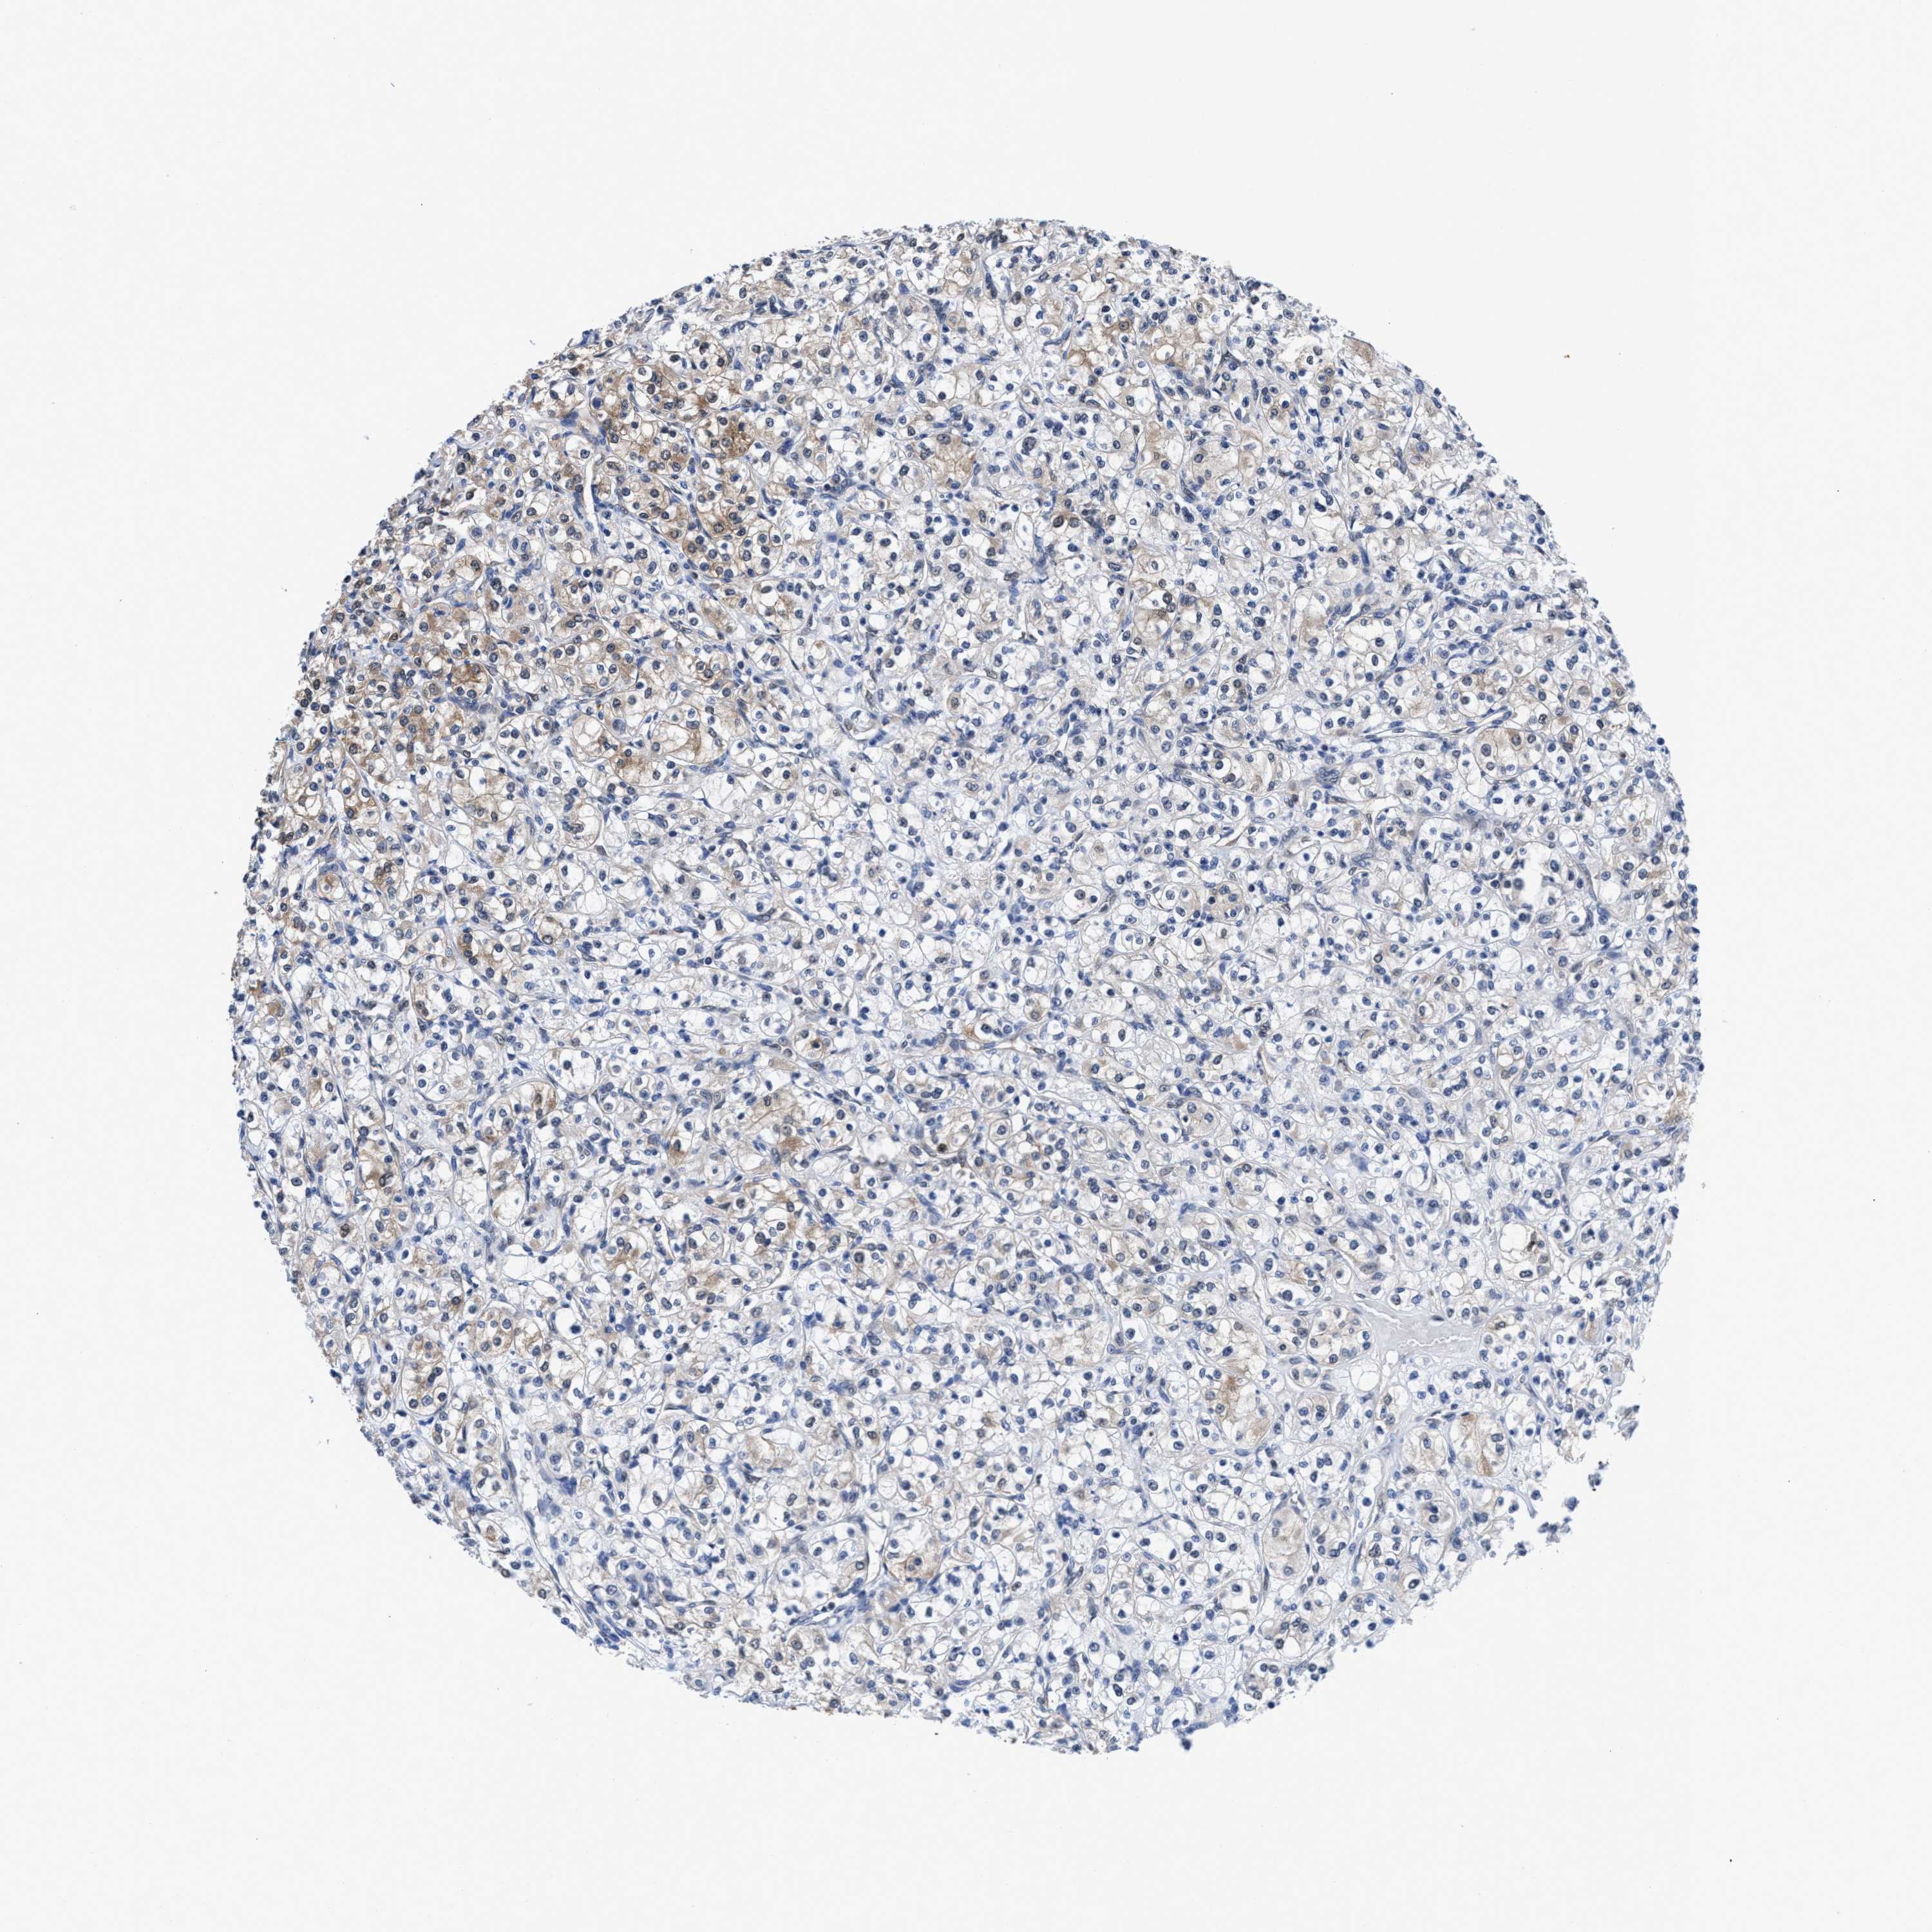

CANCER RENAL CANCER Show tissue menu

KICH TCGA KIRC TCGA KIRC VALIDATION KIRP TCGA PROTEIN RCC CPTAC PROTEIN EXPRESSION